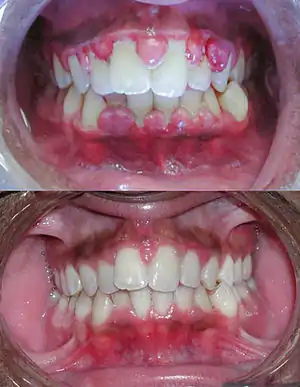

Gengivite é o processo inflamatório que ocorre na gengiva que geralmente decorre do acúmulo de placa bacteriana, também chamada de biofilme dental, devido a falta de higiene bucal adequada do indivíduo e pode estar relacionada ao estado imune do indivíduo em alguns casos. A irritação tecidual provocada pela placa bacteriana tem como principais características a alteração da coloração da gengiva que se torna avermelhada, também apresentando textura e forma alteradas. Entretanto o sangramento tende a ser o sinal mais evidente desta condição inflamatória. Pode ocorrer sangramento à sondagem realizada pelo profissional durante a consulta de diagnóstico, todavia não é incomum que o indivíduo perceba a presença do sangramento ao realizar a escovação dentária e/ou ao passar o fio dental na região interdentária.[1]

O acúmulo bacteriano é a causa principal da gengivite, porém existem outros fatores etiológicos menos comuns que também podem contribuir para o desenvolvimento da gengivite como o trauma, medicamentos, mudanças hormonais e a deficiência de vitamina C, como no caso de pacientes com escorbuto.

A gengivite é a mais comum manifestação da doença periodontal, estando associada à presença de placa bacteriana na região da margem gengival. Sondando-se o sulco gengival, este não deve ter mais que 3mm. Quando o processo inflamatório avança (profundidade de sondagem >3mm), atingindo osso, a patologia passa a chamar-se periodontite.